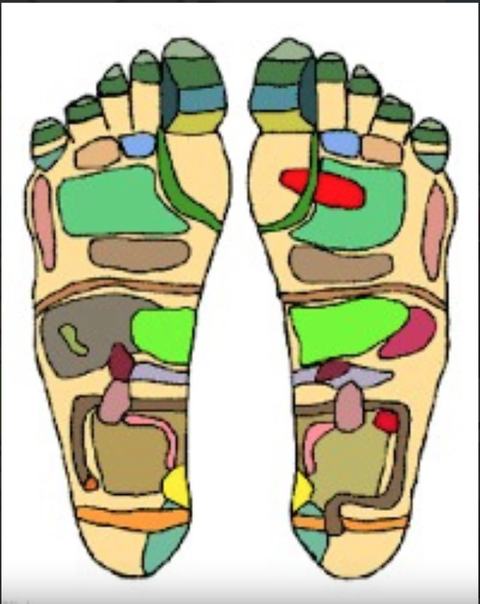

Cần chú ý chăm sóc bàn chân để nhận biết sớm bệnh trong cơ thể - Ảnh minh họa

Bàn chân là hình ảnh thu nhỏ của cơ thể

Bác sĩ Quách Tuấn Vinh, nguyên chủ nhiệm quân y Tổng cục Chính trị - cho biết bàn chân là hình ảnh thu nhỏ của cơ thể với 62 khu phản xạ, nơi khởi đầu và kết thúc của 6 đường kinh, tập trung rất nhiều đầu dây thần kinh và các huyệt vị liên quan đến toàn bộ cơ thể, từng được mệnh danh là "trái tim thứ hai" của con người.

Theo y học cổ truyền, nhất là trong châm cứu, chân có 6 đường kinh, trong đó, đáng chú ý là kinh tỳ có chức năng thống huyết (làm máu lưu thông), can tàng huyết (máu chứa ở gan) và thận tàng tinh, tinh sinh huyết.

Các nhà khoa học cho biết, ở mỗi bàn chân có tới khoảng 7.000 đầu mút thần kinh và là nơi tập trung rất nhiều huyệt vị phản chiếu tương ứng toàn bộ các cơ quan quan trọng bên trong cơ thể như tim, phổi, gan, thận...

Lòng bàn chân là nơi tập trung rất nhiều huyệt vị, phản chiếu tương ứng toàn bộ các cơ quan quan trọng bên trong cơ thể - Ảnh minh họa